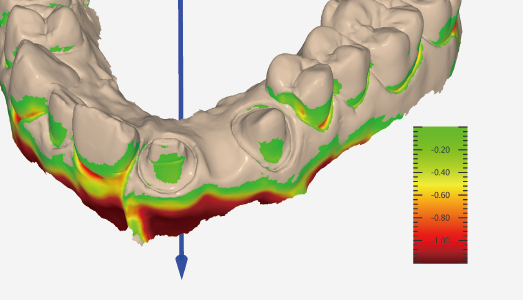

Undercut check

|